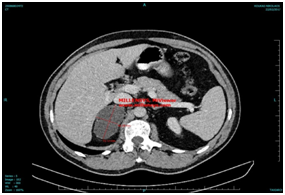

The findings where constinent of a large eggsize tumour, weight 95 gr, dimension of 8x6,5x1,8 cm, with smooth external surface. The epitheliods cells are in some locations wasllowed in dense stroma of inotic places. The immunochemistry revealed CK 27 +, Vim (+), Calretinin(=), Chromogranin (-), CK20(-), findings which represent mostly adenomatoid tumour of right adrenal gland (Figure 2).

Figure 2 The postsurgical findings can be shown in the next image.